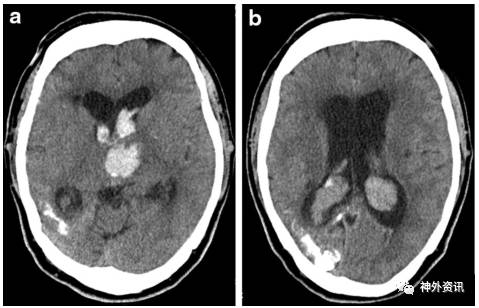

62岁患者男性,因突然昏迷入院,GCS评分6分,伴右侧轻偏瘫。在患者右侧面部三叉神经第1支分布区可见葡萄酒色血管痣,符合斯特奇-韦伯综合征皮肤表现。患者既往右眼视力下降,无青光眼、无癫痫和卒中发作病史。实验室检查提示患者有脱水表现,红细胞压积升高和D-二聚体上升。CT扫描显示左侧丘脑出血破入脑室伴急性脑积水,双侧脉络丛增大;右侧枕颞叶皮质下片状钙化(图1)。给予患者施行急诊脑室外引流术,术后7天GCS评分恢复至15分,右侧轻偏瘫逐渐好转。MRI扫描显示左侧丘脑出血、右侧颞枕叶软脑膜增强、双侧脉络丛增厚;MRA示直窦、左大脑内静脉和上矢状窦急性闭塞。予以补液和抗血栓形成治疗。2周后三维CT扫描提示直窦、左大脑内静脉和上矢状窦开放(图2)。术后3周,患者GCS评分15分,右侧轻偏瘫进一步好转,开始在辅助下行走。

图1. 头颅CT显示:a.左侧丘脑出血破入脑室伴急性脑积水;b.双侧脉络丛增大和右侧枕颞叶皮质下钙化。